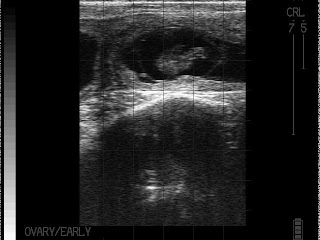

Определение стельности.

Обосновано применение ультразвука в качестве диагностики стельности с 30-ого дня. Почему нельзя раньше? Ошибочно читать, что просто не увидишь плода. Плод виден и на 25-й день. Есть две причины почему не рекомендуют раньше. Первая – это возможный натуральный аборт (на сроке 25-30 дней – максимальная предрасположенность к этому) и специалист ошибочно ведет корову к отелу как стельную. Требуется перепроверка. Конечно, перепроверять необходимо и при исследовании на более поздних сроках, но вероятность аборта выше на раннем сроке (до 30 дней). Вторая причина – это инструментальный аборт. Вероятность его минимальна, но все же существует. Дело в том, что прикрепление эмбриона к стенке матки происходит на 25-28 день. И манипуляции с маткой (особенно без опыта и осторожности) чреваты абортом. Подчеркну, что не ультразвук вызывает аборт (разумеется при нормальной интенсивности, частоте луча), а именно манипуляции.

В зависимости от размера эмбриона можно определить его примерный возраст:

28 дней:

30 дней – 1 см

35 дней – 1,5 см

40 дней:

40 дней – 2,0 см

45 дней – 2,5 см.